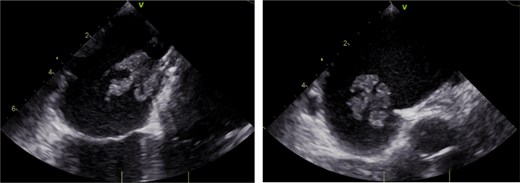

On arrival, during this hospital admission, WBC was 14.0, HR 142, Tmax 103.6. Blood cultures were positive for MSSA, and patient was started on vancomycin and ceftriaxone. Repeat blood cultures on hospital day 3 were positive for MSSA, which prompted echocardiography evaluation. Transthoracic echocardiogram was negative except for negligible tricuspid valve regurgitation. Follow-up TEE 4 days later demonstrated a mobile lesion attached to the left atrial aspect of the PFO closure device, which was concerning for vegetation (Fig. 1). Bubble study also noted a small atrial shunt. Cardiothoracic surgery was consulted and they deemed surgical explantation of the PFO device to be best-fitting.

Transesophageal echocardiogram demonstrating mobile vegetation on Gore Cardioform Septal Occluder.